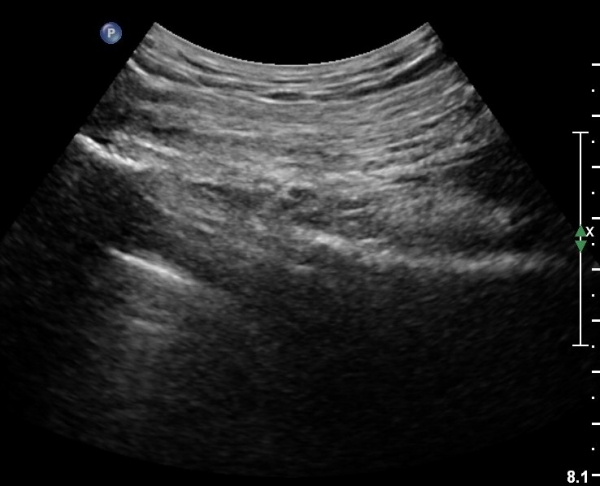

ŽÃÍÀÚ¸¦ ´Ù¸®ÂÊÀ¸·Î ¼öÆò À̵¿ÇÏ¸é ½ÉÃþ¿¡¼­ Àå°ñÀÌ »ç¶óÁö°í »õ·Î¿î ±ÙÀ°ÃþÀÌ º¸À̴µ¥ À̰ÍÀÌ ÀÌ»ó±ÙÀ̰í ÀÌ»ç±Ù ½ÉÃþ¿¡¼­ Á°ñ½Å°æ¸£ °üÂûÇÒ ¼ö ÀÖ´Ù(»çÁø 2, 3).